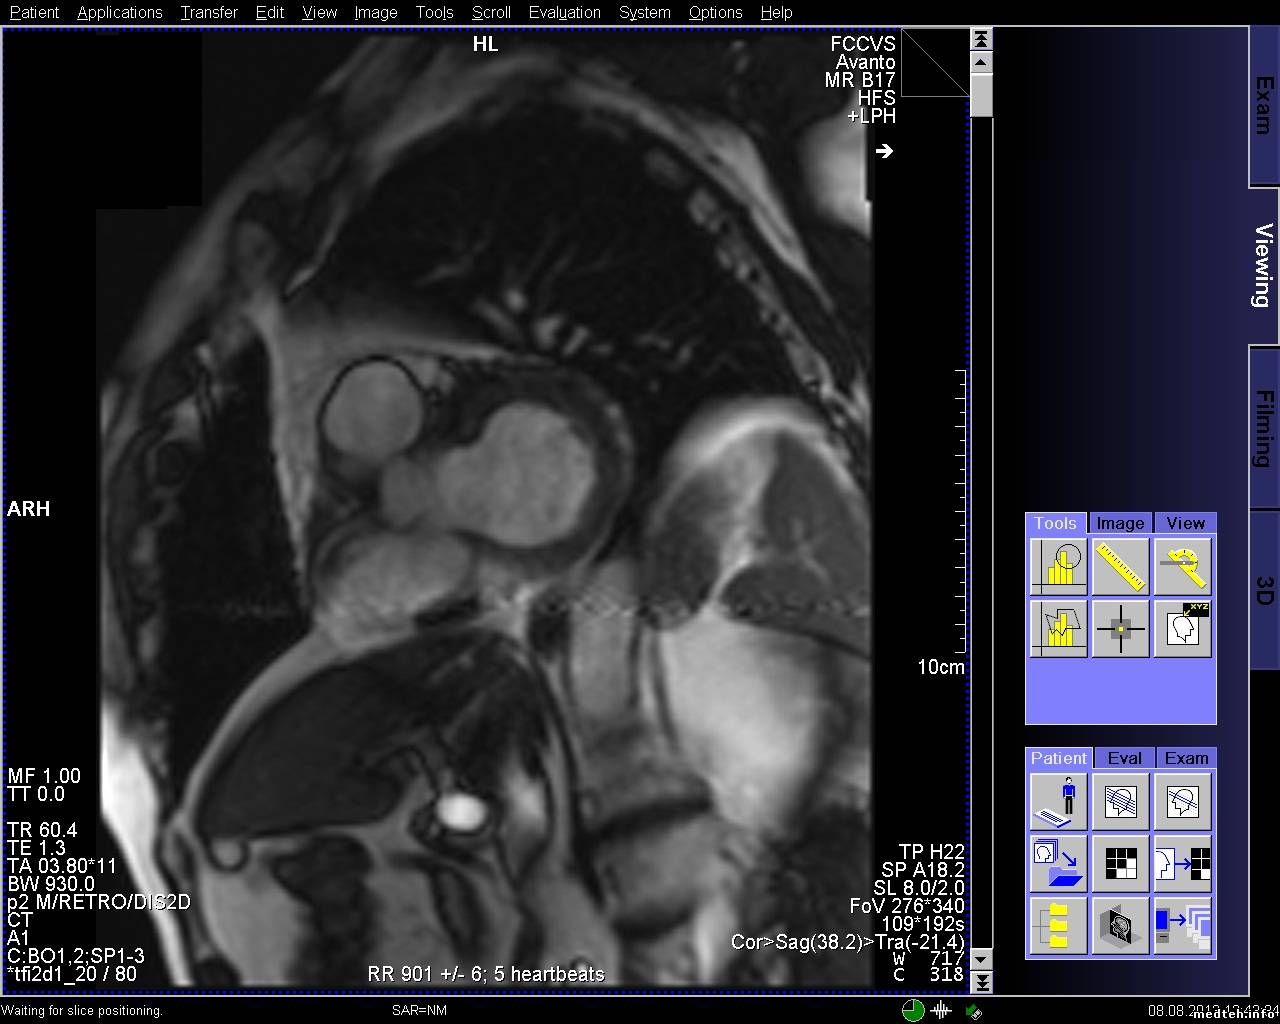

Появились артефакты на изображении при обследованиях сердца. Все тесты качества проходят.

8009364.jpg (263.4 Kb) · 5451893.jpg (273.5 Kb) · 9546723.jpg (256.9 Kb)

FedorM, спайк чек проходит, клетка в норме, источников помех нет, в том числе и светодиодных лампочек (был прецедент давненько). Полосы есть на всех направлениях срезов, но отличаются шириной и положением, могут быть узкие или широкие, могут быть сбоку от основного изображения, могут быть по средине.

FedorM, спайк чек проходит, адвансед спайк чек не проходит. Выключал свет и инъектор, пробовал в разных комбинациях включать, адвансед спайк чек так и не проходит. Полосы появляются при обследовании с контрастом, но один раз было когда смотрели шею и коленку.

Всем доброго времени суток! Проблема с полосой так и остается актуальной. По снимку и протоколу было выяснено, что частота полосы ориентировочно 20-30 кГЦ, что соответствует частоте работы градиентов. Если гонять rf-noise, то помех (полос) не наблюдается. Полосы появляются на адвансед спайк чеке. Тест гоняли только на боди катушке и при этом если просто фантом лежит, то полоса может быть, а может и не быть. Но на паценте полоса стабильно стоит. Если положить на стол длинный провод и погонять адвансед спайк чек на боди катушке, то полоса стабильно проявляется. Следовательно пациент служит как бы антенной. Частота полосы в 20 кГц наводит на мысли, что неисправность в filter plate. Подскажите пожалуйста, что, где и как ещё можно посмотреть и проверить, если неисправность в filter plate, то как его проверить?